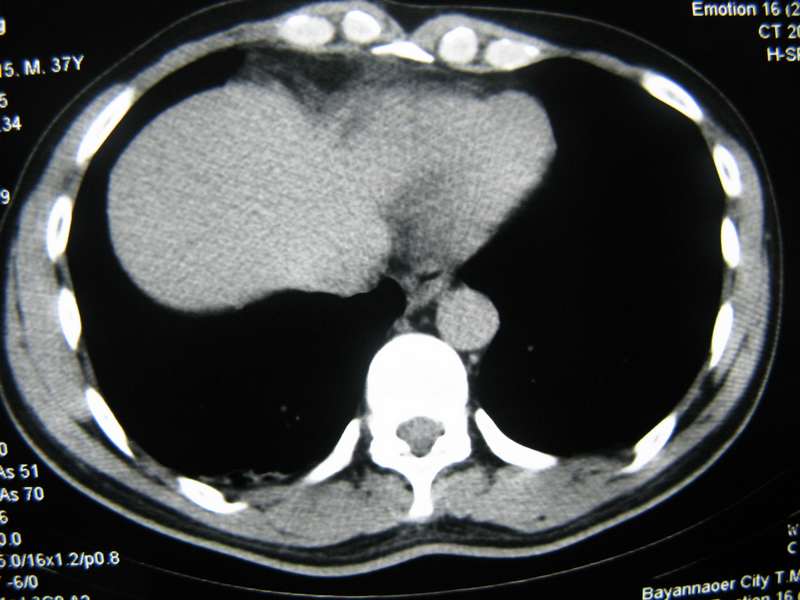

男,37岁,主述胸疼厉害,无咳嗽,无发热,血象也不高,病灶内ct值脂肪密度,右侧胸腔内少量积液,同道们考虑什么?谢谢!

脂肪垫,右下肺感染,少许积液是症状所在

纵膈脂肪堆积,右肺慢性炎症。

两肺下叶基底段纤维灶,右肺下叶基底背侧相应胸膜肥厚,右肺中叶内侧段部分不张。前中下纵隔团块状脂肪影,随访除外胸腺脂肪瘤。

纵膈脂肪堆积,右肺慢性炎症

不除外膈疝。